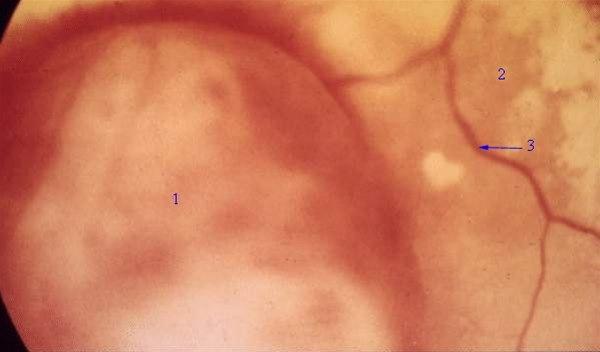

Melanom i uvea